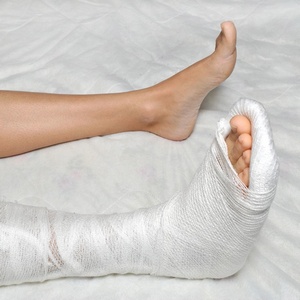

На фото обычно хорошо видно, как выглядит подобная травма. Стопа в области голеностопного сустава отечна, возможны кровоподтеки, переходящие вверх по голени. Само суставное сочленение имеет видоизмененную форму, сниженную амплитуду движения.

Наложение иммобилизации

Если у человека наблюдается неосложненный перелом, то в качестве основного метода лечения рекомендуется использовать гипсовую или полимерную иммобилизацию повязкой, которую следует наложить «сапожком».

Пациенту при этом рекомендуется стараться держать ногу в возвышенном положении для предотвращения усиления отечного и болевого синдрома.